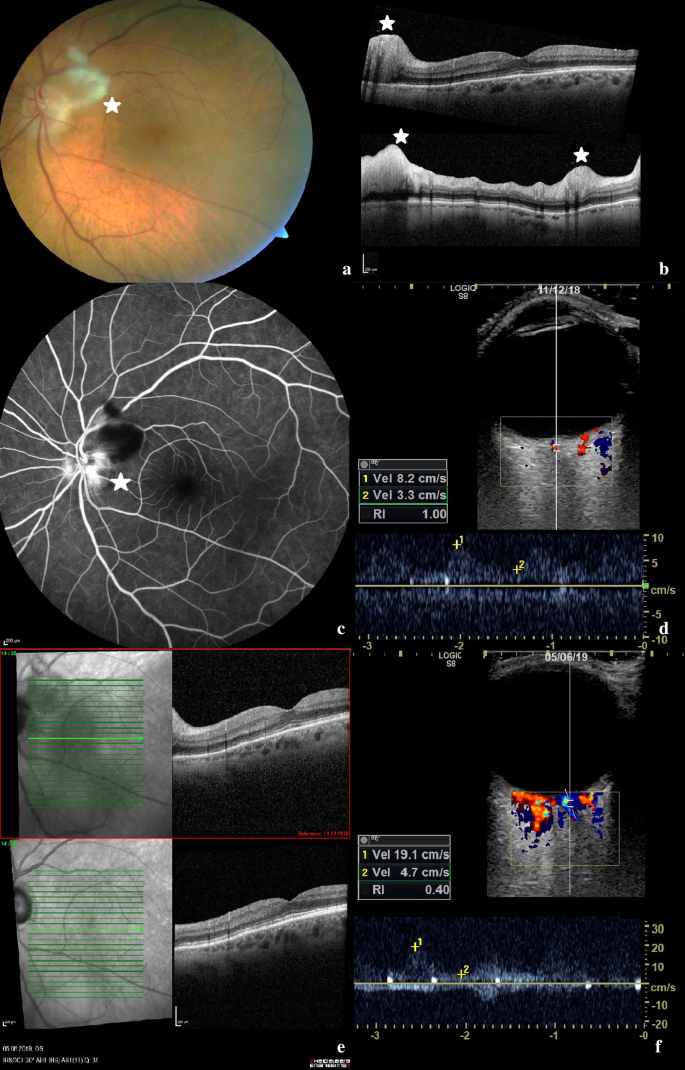

On admission, the best corrected visual acuity was 20/400 in the left and 20/25 in the right eye. Funduscopic examination of the left eye revealed optic disc edema with cotton wool spots along the upper temporal vascular arch. The macula and the retinal blood vessels appeared normal on fundoscopy (Fig. 1a).

Ophthalmologic imaging and transocular ultrasound of the left eye. a Colour fundus retinal photography of the left eye displaying an optic disc edema with adjacent cotton wool spot (*) along the upper temporal vascular arch. b Macula-optical coherence tomography of the left eye with a normal macula and segmental disc edema. Retinal nerve fibre layer thickness was increased in the superior, temporal and inferior segments (*). c Fluorescein angiography of the left eye with distinct hyperfluorescence of the papilla, i.e. a “hot disc”. d Transocular ultrasound including measurement of flow velocity of the central retinal artery of the left eye on admission. e Macula-optical coherence tomography on admission (top) compared to 6-month follow-up (bottom). f Transocular ultrasound including measurement of flow velocity of the central retinal artery of the left eye in 6-month follow-up

Optical coherence tomography (OCT) of the left macula was normal and OCT of the optic disc confirmed disc edema in accordance with the clinical appearance. Retinal nerve fibre layer thickness was increased in the superior, temporal and inferior segments (Fig. 1b) and the optic disc showed diffuse leakage (“hot disc”) on fluorescein angiography (Fig. 1c). Based on these ophthalmological findings, anterior ischemic optical neuropathy (AION) of the left eye was diagnosed.

In addition, transocular ultrasound of the central retinal artery was performed on both sides. Retinal artery displayed a systolic flow velocity of 8.2 cm/s on the left eye, and 7.5 cm/s on the right eye. This meant a marked reduction on both eyes, including the asymptomatic right eye. Until now, we have examined 25 healthy individuals with a mean systolic velocity of 14.4 cm/s (SD ± 3.2) of the central retinal artery.

The ocular ultrasound findings were in agreement with both the patient’s visual symptoms and the ophthalmological findings mentioned above.

Three months after dismissal a follow-up examination was performed. The patient was on 9 mg prednisolone per day, 162 mg tocilizumab subcutaneously per week and free of symptoms. CRP was normal. On ultrasound examination a relevant decrease of IMT values could be observed in all affected arteries. IMT of the deep lingual artery had decreased from 1.38 to 0.77 mm. Systolic flow velocities of both central retinal arteries had increased from 8.2 to 21.6 cm/s on the left eye and from 7.5 to 19.1 cm/s on the right eye.

At ophthalmological and sonographic follow-up examination 6 months after the patient´s dismissal, best corrected visual acuity increased from 20/400 to 20/40 in the left eye, the right eye was still without pathological finding. Funduscopic examination of the left eye showed a decrease of optic disc edema with a pale optic disc and narrow vessels.

OCT of the left macula revealed atrophy of inner retinal layers (Fig. 1e), while OCT of the optic disc confirmed absence of disc edema and a decrease of retinal nerve fibre layer thickness.

On ultrasound examination, a further decrease in IMT values could be observed (Table 1). Flow velocity of both central retinal arteries showed stable values with 19.1 cm/s on the left eye and 17.2 cm/s on the right eye. IMT of the deep lingual artery had decreased from 0.77 to 0.34 mm.

Further is this the first case in literature in which vasculitic vessel wall edema of the central retinal artery was visualized, which markedly decreased over 3 and 6 months under therapy. The patient´s symptoms rapidly disappeared including the dry cough which has been described in 14% of GCA patients and often occurs before other symptoms appear [13, 14].

As highlighted by the improved systolic flow velocity of the central retinal artery on follow-up, ischemia of the optic nerve was likely not permanent and improved under treatment, which might explain the good visual recovery. To this point there is no literature examining the ultrasound measurement of the flow velocities of the central retinal artery, but there seems to be a significant decrease in flow velocities, as recently published at the EULAR congress in 2020 [15].